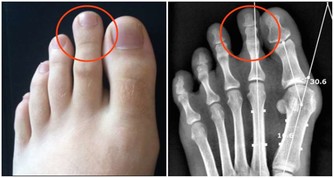

7. 皮膚癌:皮膚出現變化

我們臉上的痣和雀斑很少生長,改變顏色或大小。如果它們出現變化,並且不會消失,就要當心癌症。尤其是皮膚白皙的人,出現黑色素瘤的風險比較高。此外,請注意,並非所有黑色素瘤都會改變形狀或大小,所以最好還是每年檢查。